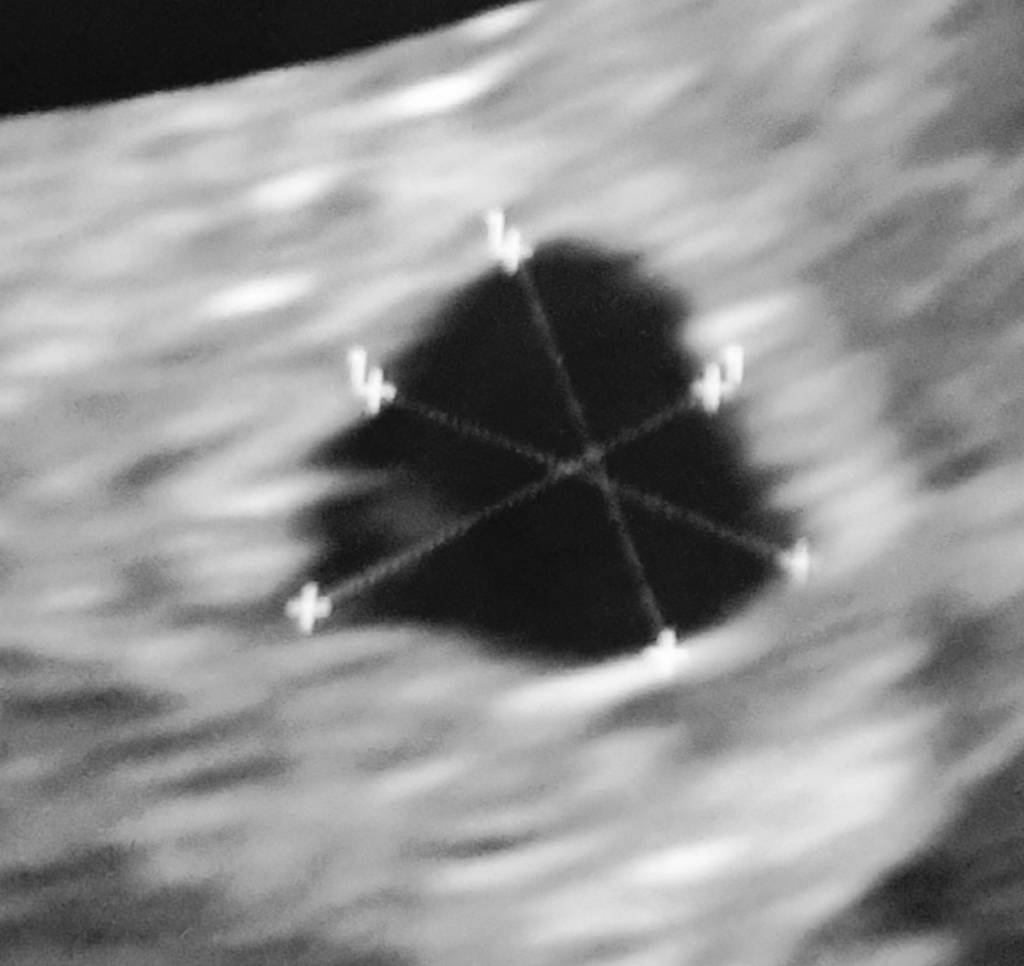

Dziewczyny moja koleżanka która jest specjalistką we wczesnych ciążach mnie troszku pocieszyła i powiedziała że mam woreczek żółtkowy który wygląda jak pierścionek A to bardzo dobry znak więc mam nadzieję. Jutro mam jeszcze jedną wizytę u ginekologa ale raczej nie będę robić USG po prostu chcę L4 do poniedziałku bo psychicznie nie dam rady

Dziewczyny moja koleżanka która jest specjalistką we wczesnych ciążach mnie troszku pocieszyła i powiedziała że mam woreczek żółtkowy który wygląda jak pierścionek A to bardzo dobry znak więc mam nadzieję. Jutro mam jeszcze jedną wizytę u ginekologa ale raczej nie będę robić USG po prostu chcę L4 do poniedziałku bo psychicznie nie dam radyZobacz załącznik 1246383Zobacz załącznik 1246384

Ja też coś widzę zagnieżdżenie w macicy